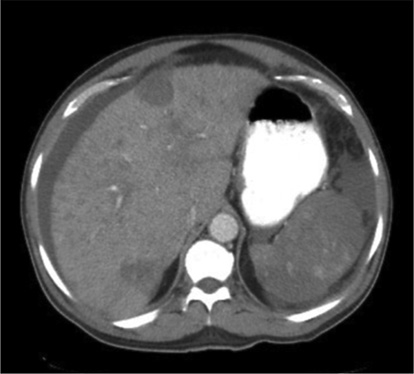

- 中年女性无症状肝脏多发病灶,原因为何? 医脉通-临床病例平台患者女,45岁,因影像学检查偶然发现肝脏多发病灶就诊。患者无相关症状,体格检查正常。……